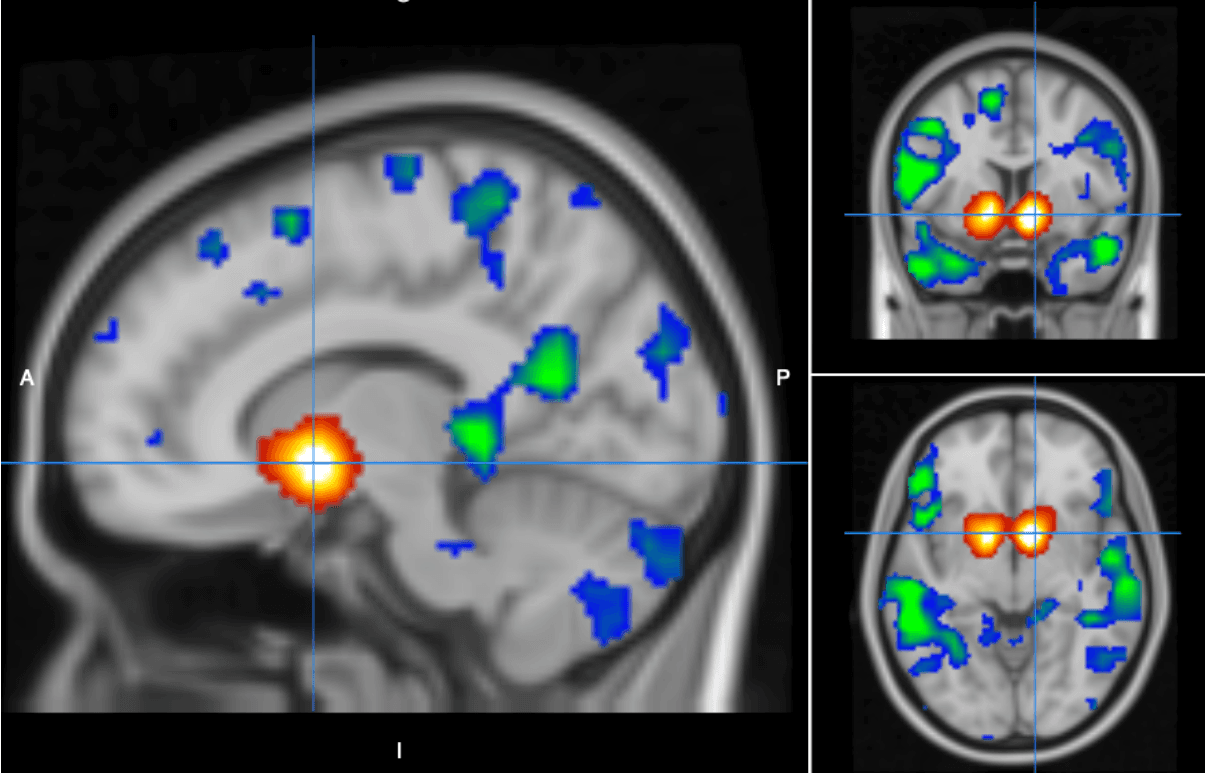

Play some simple computer games in the brain scanner and join us in exploring how decision-making activates the brain — and maybe win some money in the process.

The experiment takes place on two days and it takes 2.5 hours per day. Background and purpose of the experiment: Aim: Examine brain activity in an MRI scanner during six decision-making and learning tasks. Tasks involve: - Quick responses to images. - Learn about the meaning of different images. - Choosing between safe and risky gambles. Experiment plan: Duration: The experiment takes place on two days and takes 2.5 hours per day. Day structure: - Play two games in the scanner (~50 minutes) - Have a break - Play one more game in the scanner (~25 minutes) and afterward do questionnaires, while we collect anatomical images (~ 20 minutes). You can expect 10 to 15 minutes each day for introductions and debriefing.